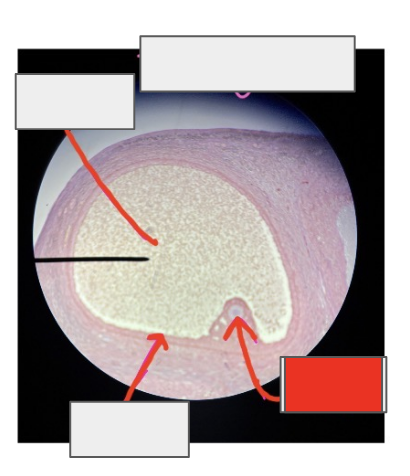

ovary

What organ is this from?

Tertiary follicle

what is this whole thing?

Primary oocyte

Granulosa cells

Antrum